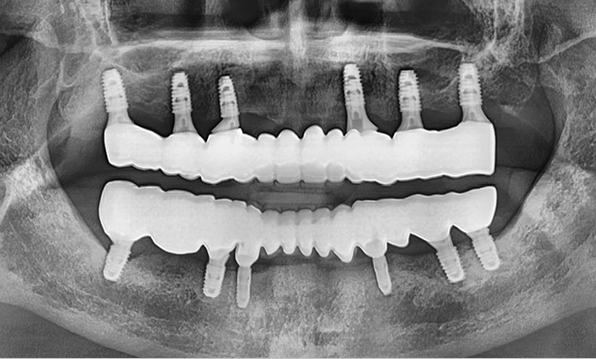

Full PlacementUsing a method of placing 8–9 implants in the maxilla and 8 implants in the mandible, this approach fully restores all 28 natural teeth, creating an oral environment most closely resembling

natural dentition. -